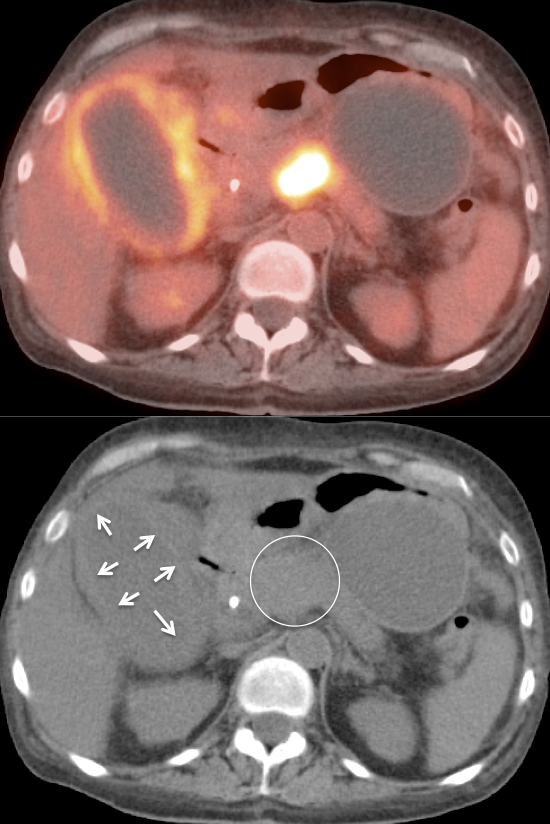

Gallbladder Cancer

Fast Facts:

- Most common biliary tract malignancy.

- Extremely lethal if symptomatic at presentation (mean survival ≈ 6 months).

- Associated with gallstones and chronic inflammation (incidentally found at surgery in ≈ 2% of routine cholecystectomy patients).

Initial Staging of Gallbladder Carcinoma:

- While PET/CT can detect the primary lesion, its true utility lies in the detection of regional nodes and distant metastatic disease.

- Distant Disease: Most commonly to the liver, lung and brain.